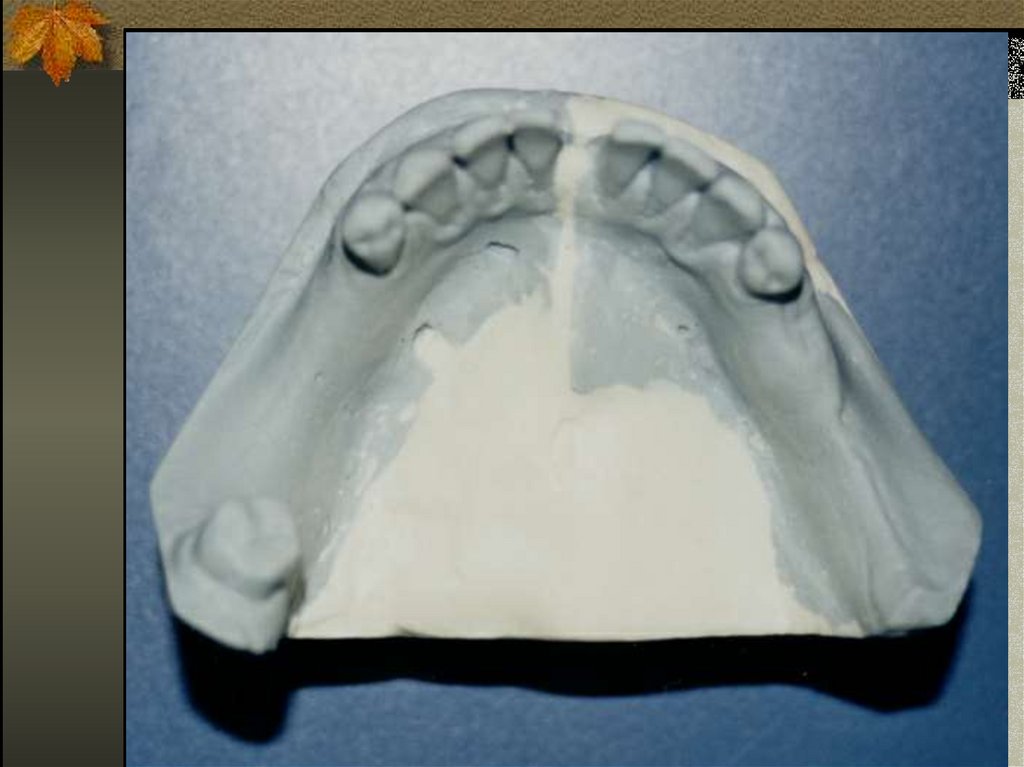

19. GUNNING SPLİNT

20.

21. DÖKÜM REHBER APAREYİ

22. DAMAK PLAĞI ŞEKLİNDE REHBER APAREYİ